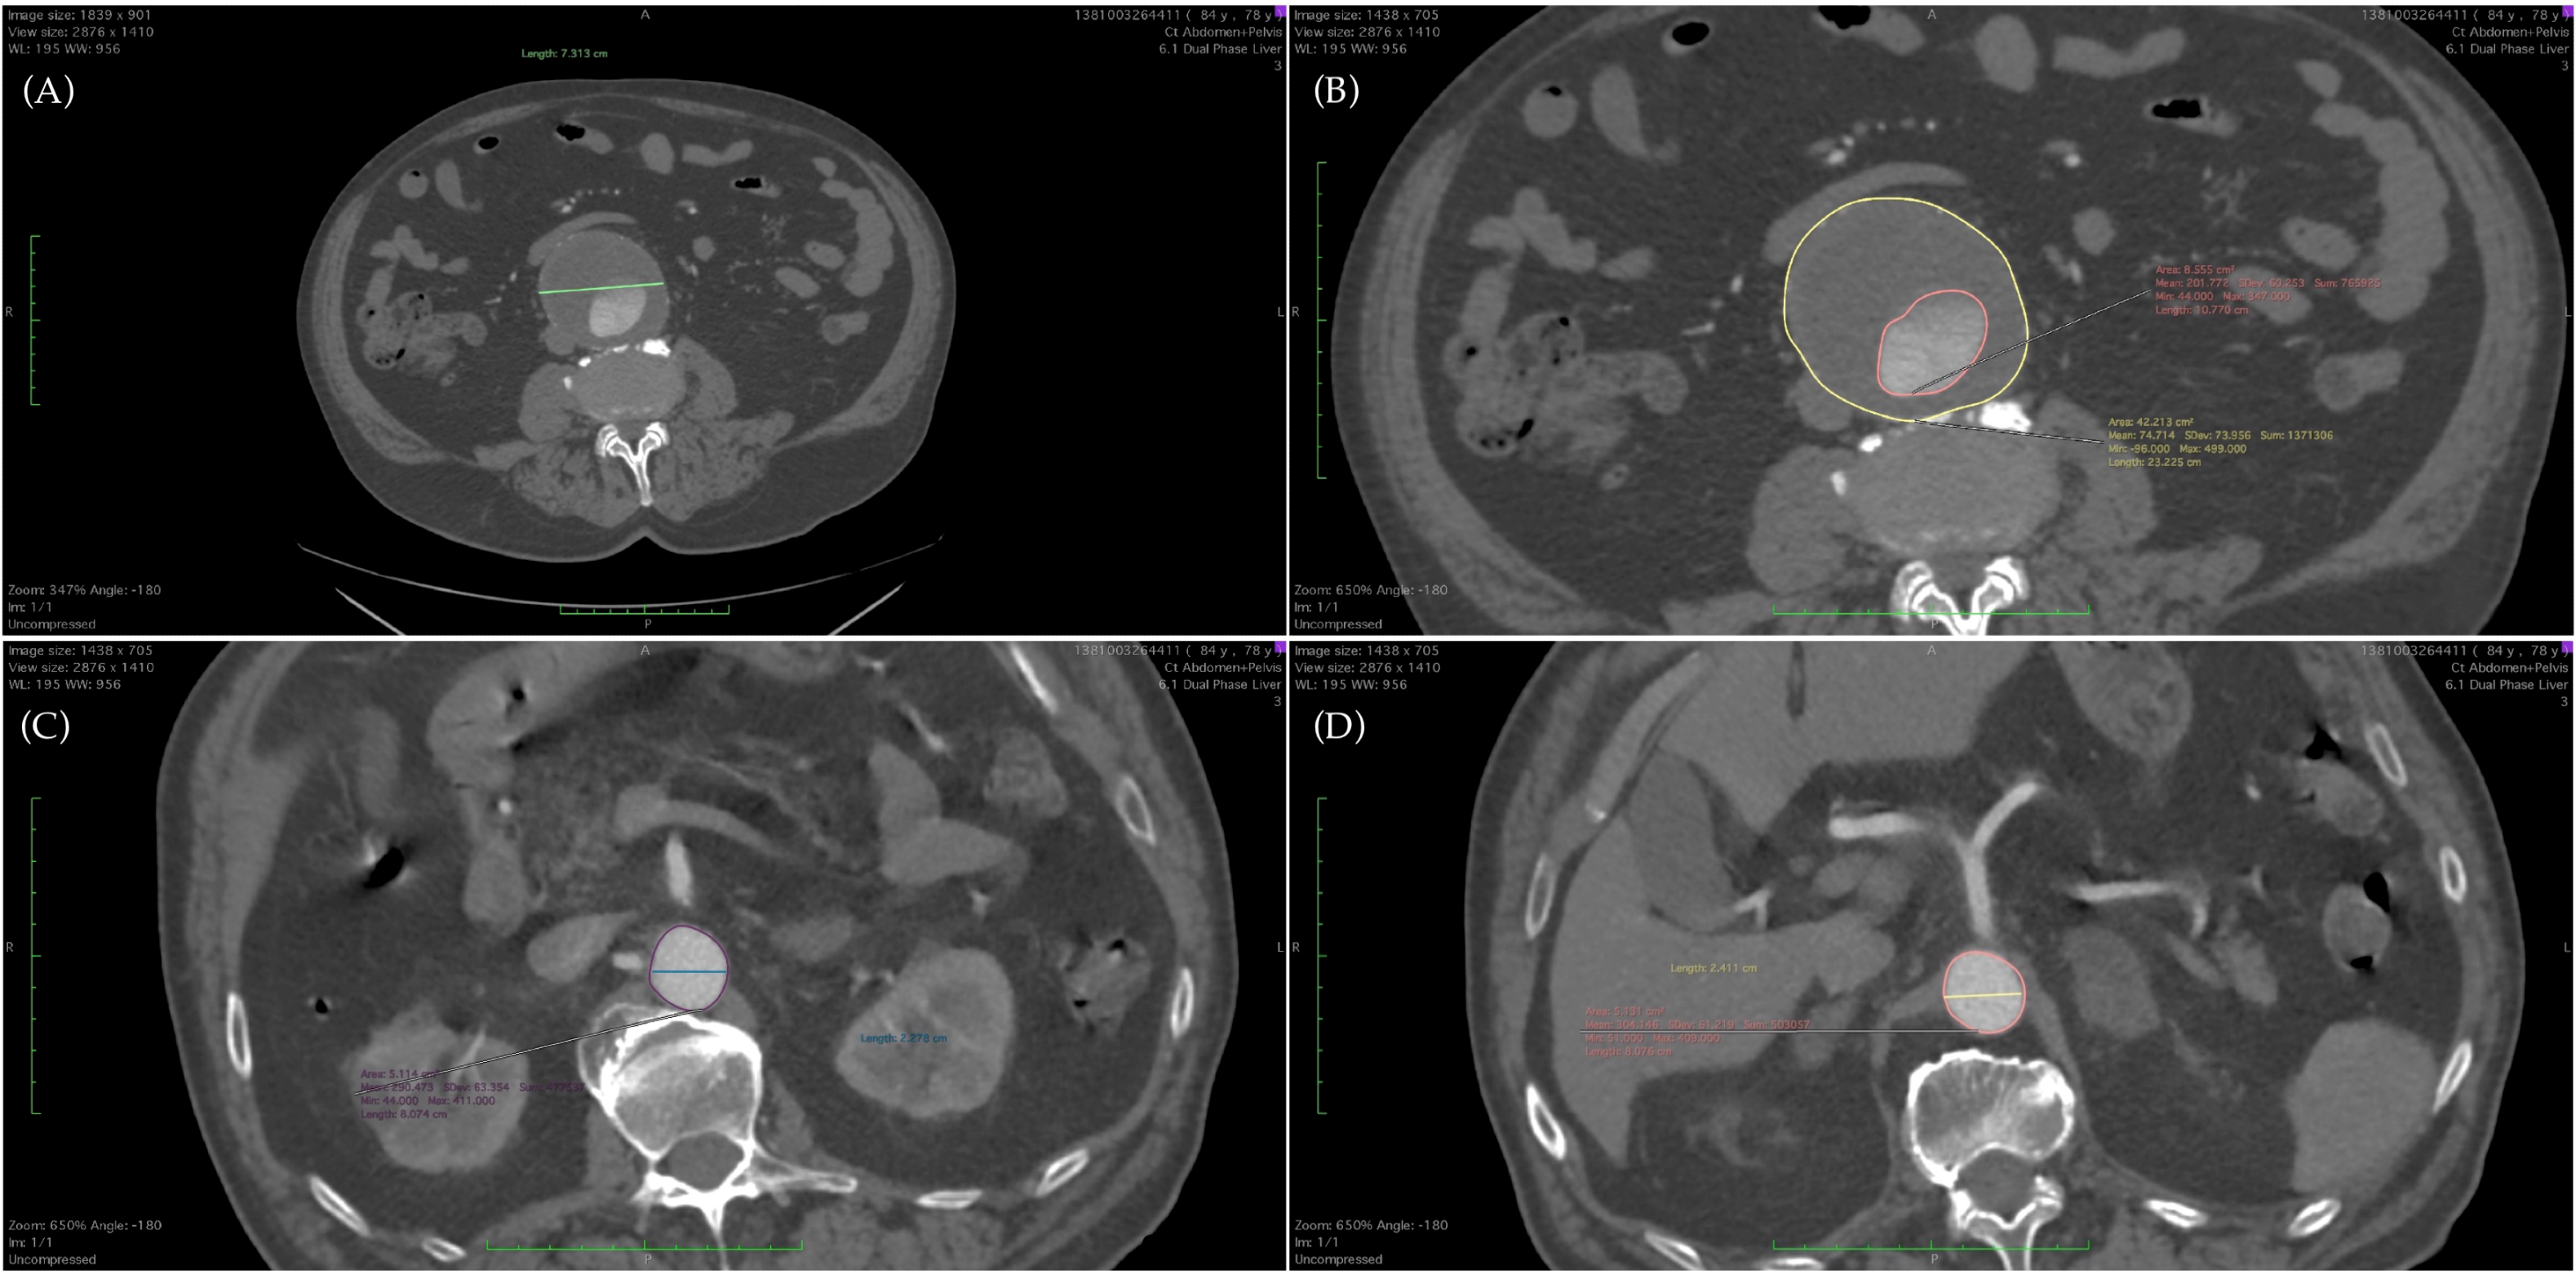

| Markers | Definition |

|---|---|

| DAmax | maximum diameter of the AAA |

| DArenal | diameter of the aorta at renal level |

| DACT | diameter of the aorta at celiac trunk level |

| DAfemoral | diameter of the femoral artery |

| SAmax | surface of the AAA at maximum diameter |

| SArenal | surface of the aorta at renal level |

| SACT | surface of the aorta at celiac trunk level |

| SAfemoral | surface of the femoral artery |

| SLumenmax | surface of the lumen at maximum diameter of the AAA |

| SThrombusmax | surface of the thrombus at maximum diameter of the AAA |

| DAmax/Arenal | |

| DAmax/ACT | |

| SAmax/Arenal | |

| SAmax/ACT | |

| SAmax/Lumenmax | |

| SLumenmax/Thrombusmax |